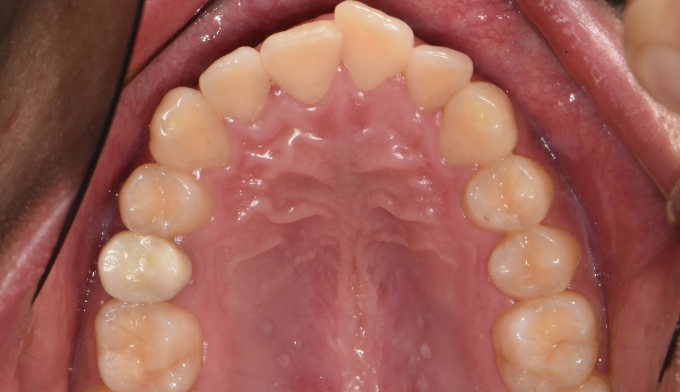

앞니불규칙

앞니를 배열하는데 있어서 필요한 공간이 많지 않은 경우, 전체교정 없이 앞니만 부분적으로 교정하는 방법을 통하여 쉽고 빠르게 치열을 가지런하게 할 수 있습니다. 멀쩡한 앞니를 삭제하고 씌우는 크라운이나 라미네이트 치료를 하지 않아도 됩니다.

교정기간은 7개월 소요되었습니다.